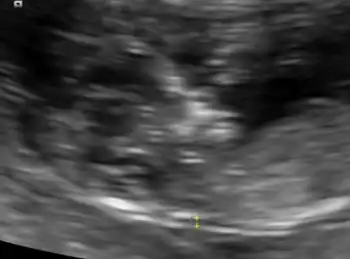

An ultrasound showing a fetus with hydrops fetalis

Hydrops foetalis is severe accumulation of fluid in an unborn baby.[1][2] By comparison, hydrops allantois or hydrops amnion is an accumulation of excessive fluid in the allantoic or amniotic space, respectively.[3]